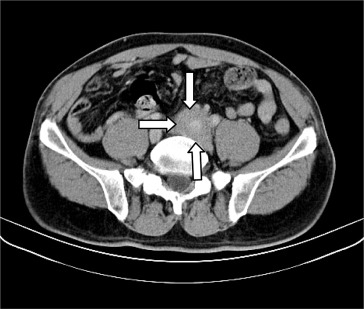

Infiltrate soft tissue around the left common iliac artery (arrows).

Figure 2.

Physical examination showed icteric sclera, generalized yellowish discoloration of skin, and no abnormal finding was found. Laboratory data included 8.1 × 109 /L white blood cells (normal, 4.0–10.0 × 109 /L), 55 U/L aspartate aminotransferase (normal, <35 U/L), 181 U/L alanine aminotransferase (normal, <40 U/L), 349 IU/L alkaline phosphatase (normal, <128 IU/L), 356 U/L ɣ-glutamyltransferase (normal, <60 U/L), 9.1 mg/dL total bilirubin (normal, <1.6 mg/dL), and 80 U/L amylase (normal, 30–110 U/L). Marked elevated serum IgG4 was also noted (5660 mg/L; normal, 39.2–864 mg/dL). Abdominal computed tomography (CT) and magnetic resonance cholangiopancreatography demonstrated diffuse enlargement of the pancreas with dilatation of the biliary tree and without pancreatic duct dilatation (Fig. 1 ). An unusual infiltrating soft tissue around the left common iliac artery causing left hydronephrosis and hydroureter was noted also (Fig. 2 ). Percutaneous transhepatic biliary drainage was performed for jaundice relief by an emergency physician. Endoscopic retrograde cholangiopancreatography showed narrowing of the lower common bile duct and pancreatic duct lumen (Fig. 3 ). A plastic stent (preloaded Cotton–Leung biliary stent, C741707, 7F, 7 cm) was implanted for biliary drainage. Several days later, a linear endoscopic ultrasound identified marked swelling of the pancreatic head and body with heterogeneous echogenicity and no pancreatic duct dilatation. A biopsy of pancreatic tissue was not performed due to patient intolerance. Biopsy of the soft tissue surrounding the left ureter was done under CT guidance, and histopathological examination showed diffuse lymphoplasmacytic infiltration of soft tissue and obliterative phlebitis with a positive IgG4 stain over the plasma cell (Fig. 4 ). Hence, the patient was administered methylprednisolone 40 mg/day initially and his symptoms improved. A repeat abdominal CT examination showed that his pancreas and soft tissue near the left common iliac artery had shrunk after treatment for 3 months. (Fig. 5 )